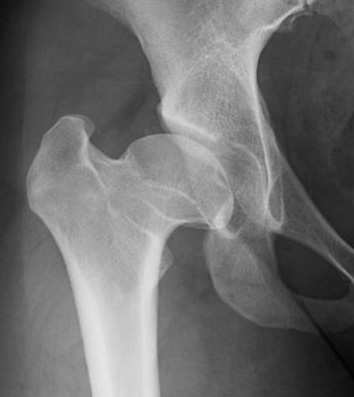

Perthesova choroba, plným názvem Legg-Calvé-Perthesova choroba, je ortopedické onemocnění, které se nejčastěji vyskytuje chlapců ve věku 4 až 8 let a postihuje kyčelní kloub. Základním problémem Perthesovy choroby je dočasná ztráta krevního zásobení do hlavice stehenní kosti (části stehenní kosti, která vstupuje do kyčelního kloubu). V...